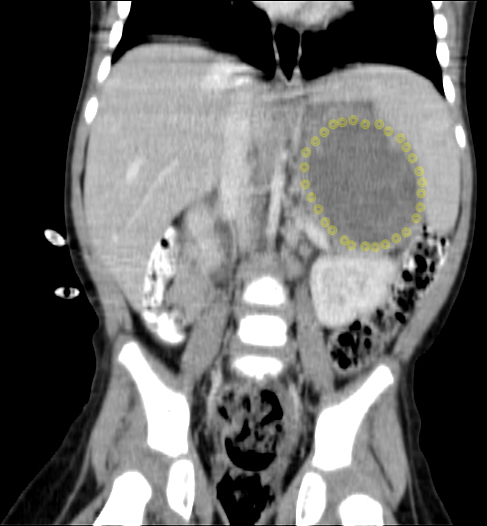

CT (CAT) scan 25 August 2011